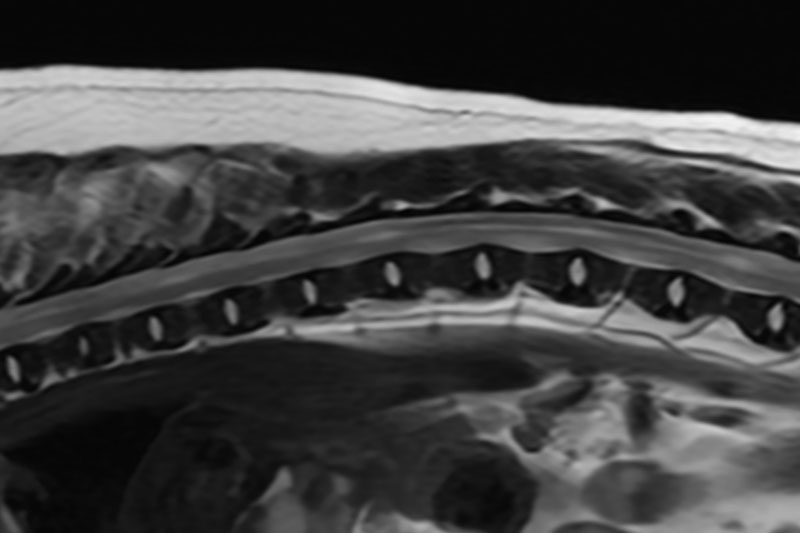

| 척수/신경계 | 디스크 탈출, 척수압박, 척수염, 척수종양 등 |

관절·인대·연골 등 운동계 미세 손상 진단